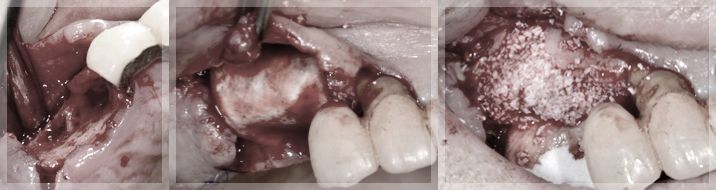

右上4相当部GBR

インプラントは骨に支えられることで機能します。しかしインプラントを支えるだけの骨が残っていない場合もあります。そのような場合骨を造成する処置を行うことでインプラント治療をすることが可能になります。

今回の場合でも骨を造成する処置を行っております。この処置においても麻酔をしっかりとするので痛みを感じることなく処置が行えます。骨が作られるまでの間3ヶ月ほど待機することになりますので早期に処置を行うことで治療期間を短縮することができます。

上顎前歯インプラント埋入 GBR

下の前歯が綺麗に並んできています。上の前歯もインプラント治療を行います。上の前歯も骨造成を行った上でインプラント治療をしていますがその間仮歯によって見た目は保たれている状態です。

上の前歯の見た目やインプラントが長期的に機能するために移植を含めた歯茎の処置を行っています。